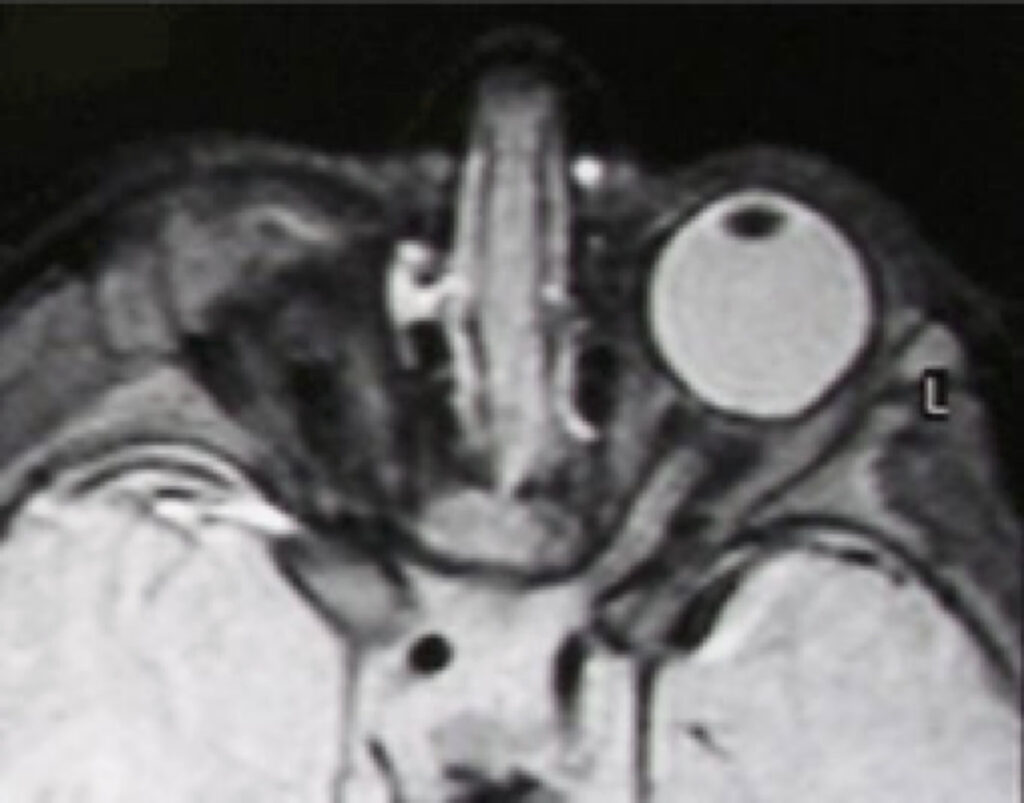

This young lady was treated with serial expansion for her left microphthalmic eye and socket.